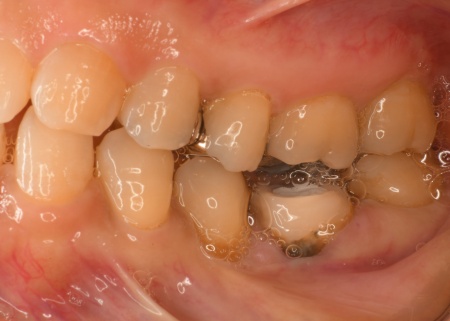

治療前

治療中

「左下の歯を過去に治療したが、虫歯が再発してしまった。現在治療途中だが、痛みが続いて不安なため、こちらの歯科医院で診てもらいたい」とご相談いただきました。

拝見したところ、左下の奥歯に「根尖性(こんせんせい)歯周炎」が生じ、痛みの原因になっていると考えられました。

根尖性歯周炎とは、神経が死んでしまった歯や神経を取って治療した歯の内部に細菌が侵入し、歯根の先端が炎症を起こす病気です。

このままだと炎症がさらに広がって痛みが強くなり、最終的には歯を失うおそれもあるため、早急な治療が必要であると判断しました。